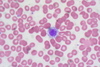

A 36-year-old woman comes to the clinic for a routine check up. She feels well but reports that she has noticed that she is bruising more easily. Medical history is noncontributory. She takes a multivitamin daily. Skin examination shows scattered petechiae on all extremities. Laboratory serum studies show a leukocyte count of 9,000/mm3, hemoglobin 12.0g/dL, platelet count 75,000/mm3, prothrombin time 12 seconds, and INR 1.0. A peripheral blood smear is obtained and is shown below. Which of the following is the most likely underlying mechanism of her condition?

Autoimmune destruction of platelets

Idiopathic thrombocytopenic purpura (ITP) presents with epistaxis, gingival bleeding, petechiae, and easy bruising. ITP occurs secondary to autoimmune destruction of circulating platelets.